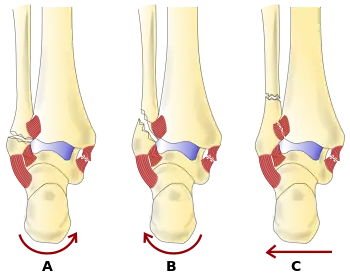

There are several classification schemes for ankle fractures. Out of the following, the Lauge-Hansen and Danis-Weber classification systems are most commonly used.[8]

- The Lauge-Hansen classification categorizes fractures based on the mechanism of the injury as it relates to the position of the foot and the deforming force (the most common type is supination-external rotation)

- The Danis-Weber classification categorizes ankle fractures by the level of the fracture of the distal fibula (type A = below the syndesmotic ligament, type B = at its level, type C = above the ligament), with use in assessing injury to the syndesmosis and the interosseous membrane